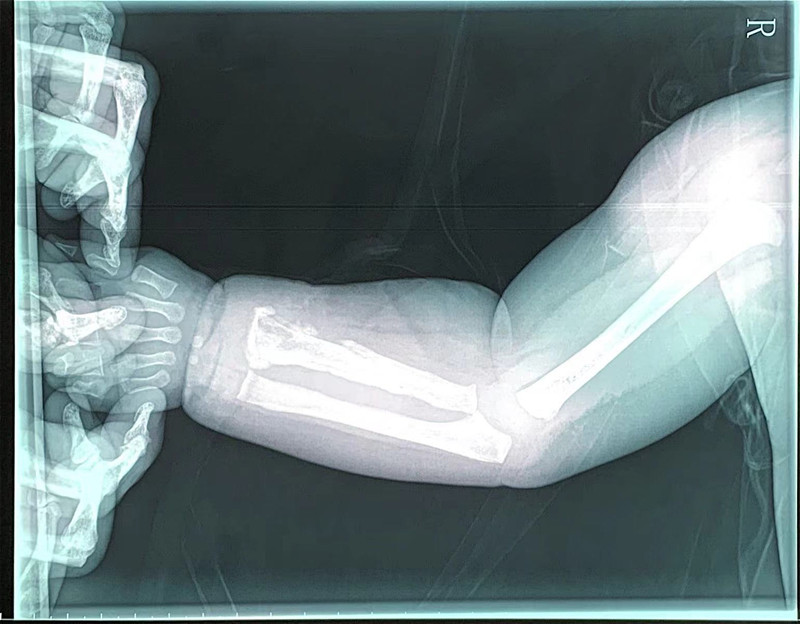

7月13日上午,1岁男宝小宇(化名)住进了蜜桃视频 骨、泌尿、烧伤科,他不明白为什么自己的胳膊会又疼又肿,更不知道一种叫“急性骨髓炎”的疾病正在侵扰着他。

局部切开,减压、引流

小宇一周前发过烧,后来胳膊肿了。小宇妈妈说,原以为孩子只是普通感冒,打针后烧退了,但胳膊一直不见好转。这种情况,医生怀疑是急性骨髓炎。拍片显示,其桡骨骨质改变,结合核磁检查结果,医生综合分析,明确是急性骨髓炎。由于已错过发病初期48小时最佳治疗期,不能保守治疗,医生建议马上手术。随后,副主任医师高凤奇为小宇手术,局部切开、病灶清除、开窗减压、置管冲洗引流,术后又进行抗感染治疗。2周后,小宇症状改善,无肿痛、无化脓液,基本痊愈。